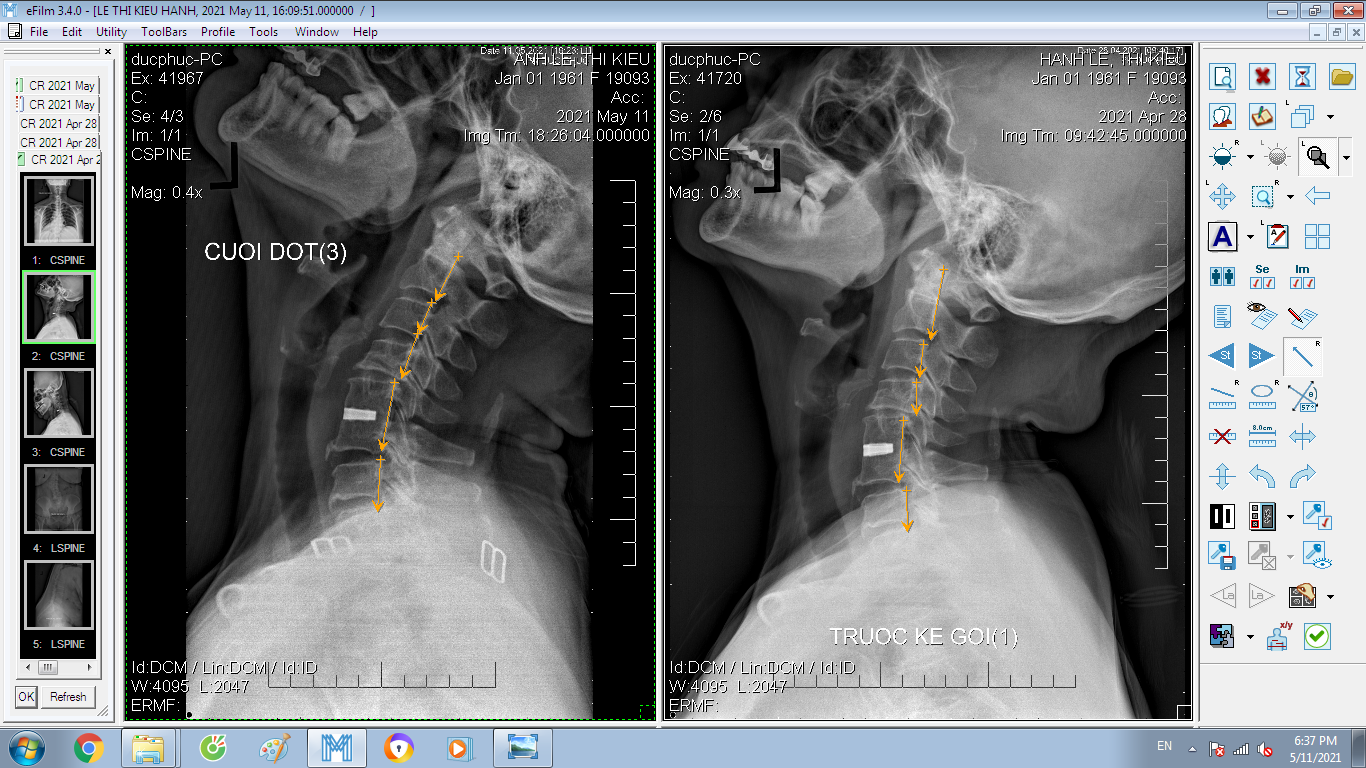

DOCTORLOAN đã thành công trong điều chỉnh xương khớp về đúng vị trí trong thời gian ngắn